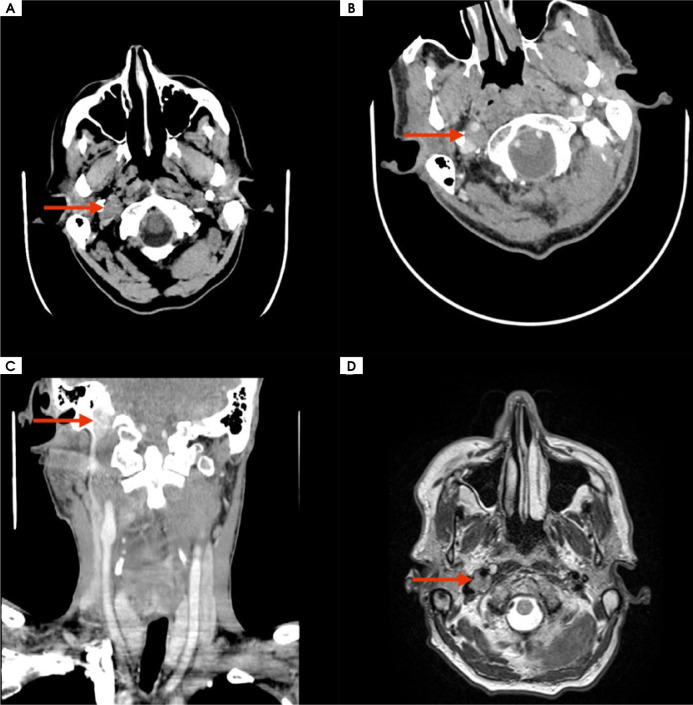

Case description: A 58-year-old male presented with a four-month history of progressive dysphagia and dysphonia. Neurological examination revealed cranial nerve IX, X, XI and XII palsy. Imaging demonstrated a focal lesion situated between the internal carotid artery and the jugular vein, ultimately diagnosed as diffuse large B-cell lymphoma. The patient was referred for hematological treatment.